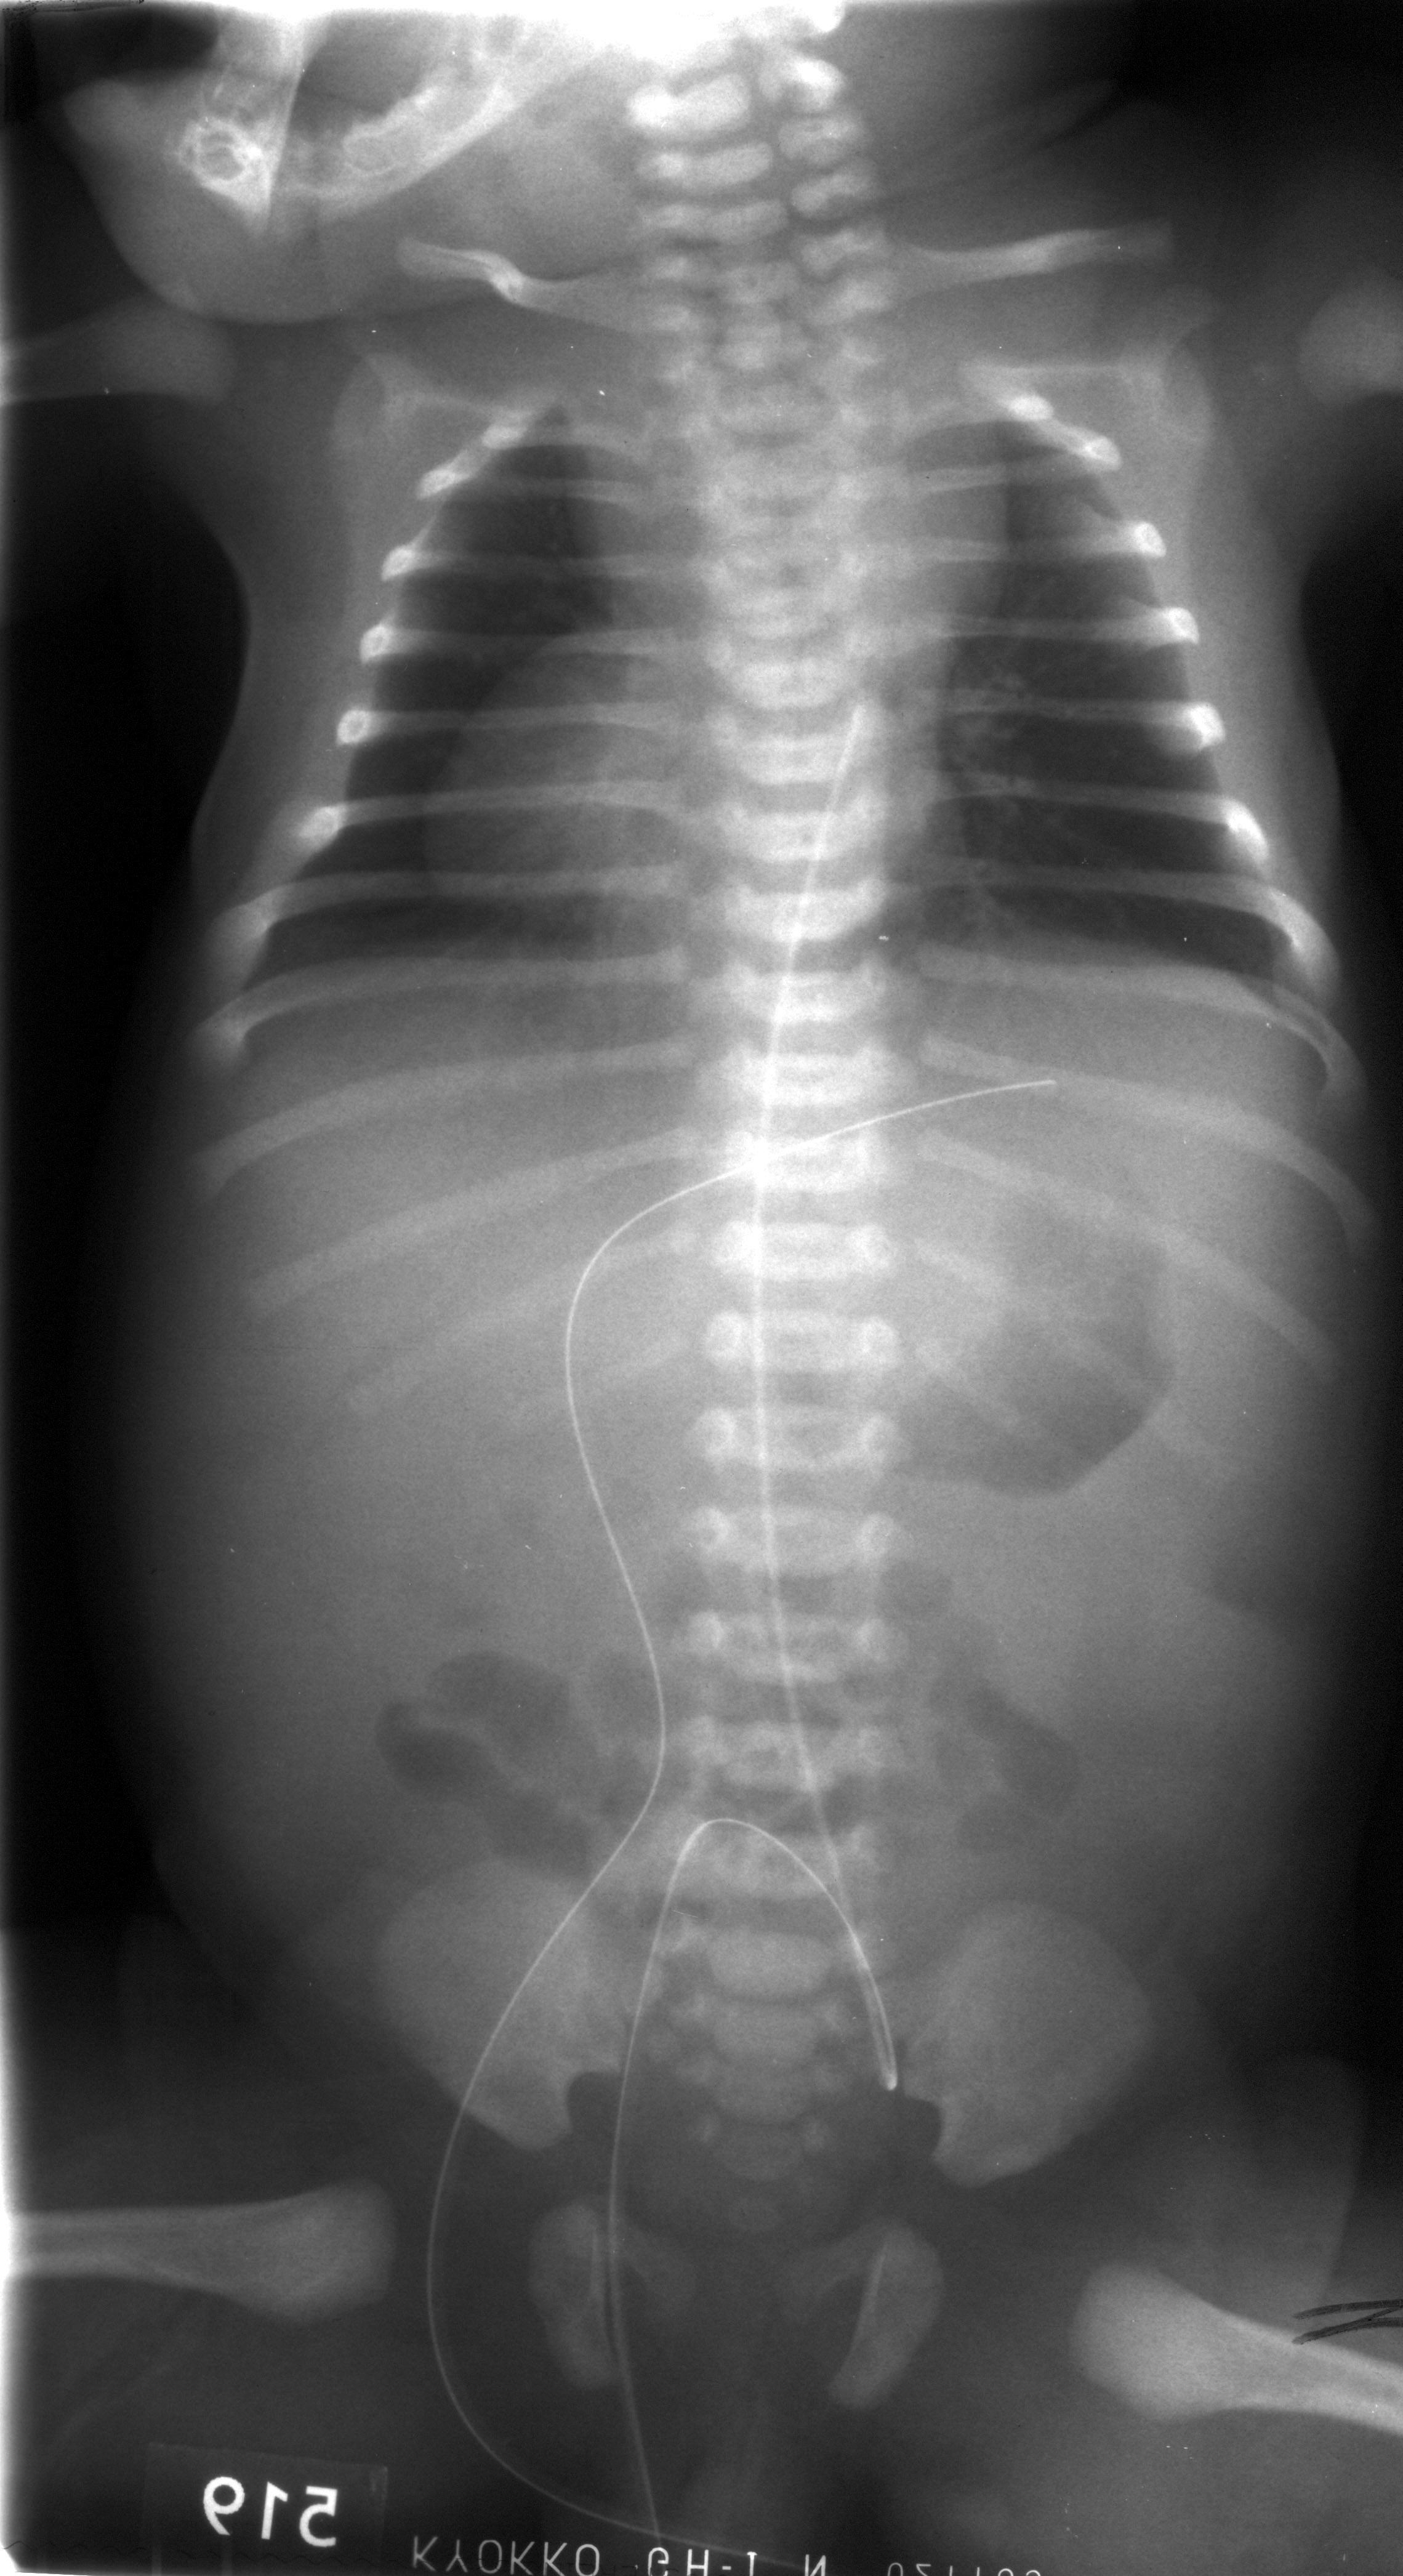

Декстрокардия

Декстрокардия 116 фото